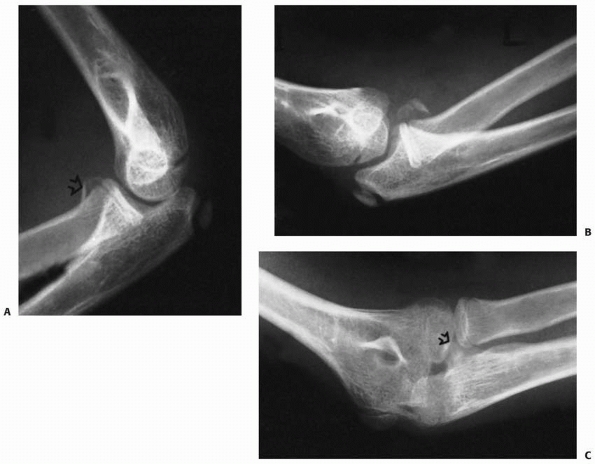

FIGURE 11-8 Dislocation fracture patterns. A.

Type D: The radial neck is fractured during the process of reduction by the capitellum pressing against the distal lip of the radial head.125 B. Type E: The radial neck is fractured during the process of dislocation by the capitellum pressing against the proximal lip of the radial head.98 C. Radiographs of a radial head that was fractured during the reduction of the dislocation (type D). The radial head (solid arrow) lies posterior to the distal humerus, and the distal portion of the neck (open arrow) is anterior. (Courtesy of Richard E. King, MD.) D. Radiograph of the dislocated elbow in which the fracture of the radial neck occurred during the process of dislocation (type E). |